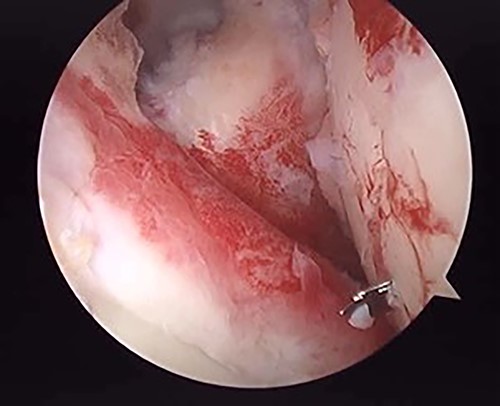

The operation was performed under general anesthesia with an ultrasound-guided brachial plexus block in the beach chair position. First, we performed intra-articular observation by arthroscopy with a 30° scope. Through a posterior portal, we confirmed incongruence of the articular surface of the humeral head, similar to the preoperative findings in 3D-CT (Fig. 4). On the other hand, the posterior joint labrum and glenoid rim were intact. After evaluating the intra-articular lesion, we performed arthroscopic reduction for the impression fracture at the humeral head via the arthroscopic method [5,6]. We split the deltoid muscle and exposed the lateral surface of the humerus. We inserted a Kirschner wire as a reduction guide 2 cm distal from the upper border of the greater tuberosity and 2 cm behind the bicipital groove (Fig. 5). Kirschner wire was inserted to exit the impression lesion while checking the articular surface with an arthroscope (Fig. 6). We created a cortical window (approximately 10 × 10 mm) using a cannulated drill with the Kirschner wire as a guide. To reduce the impression, we pushed the back of the impression using the flat side of the canulated cancellous screw (CCS) drill. After the reduction, artificial bone was inserted from the cortical window to the subchondral bone region to provide support for the depressed area. We then performed a procedure to insert a support screw into the articular surface. The deltopectoral approach was used. First, we dissected the subacromial bursa entirely while visualizing the conjoint tendon. Next, we detached the long head of the biceps at the bicipital groove and sutured it to the pectoralis major muscle. Two CCSs were inserted from the bicipital groove to under the repaired humeral head as support for the reduction site. Finally, after arthroscopic reduction, we performed ORIF for surgical neck fracture using a PHILOS Plate™ (DePuy Synthes).

Posterior arthroscopy of the right shoulder joint showing a reduced depressed surface and the Kirschner wire for reduction guide.